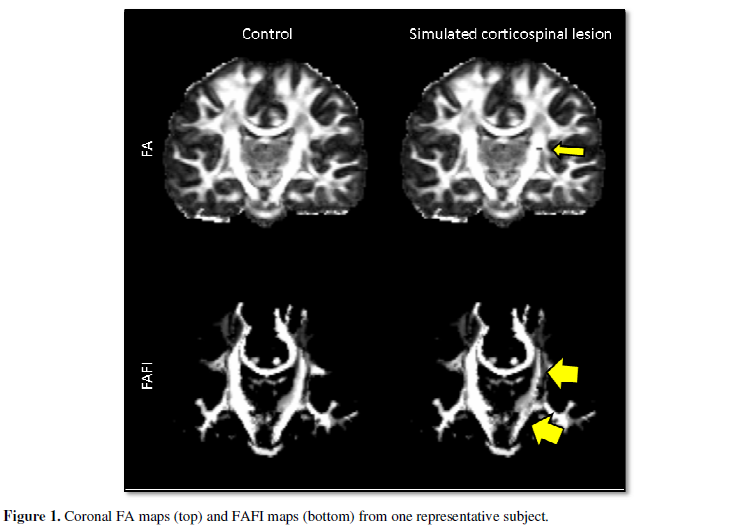

Simulated lesions were fairly

small, with mean lesion volume of 147 mm3 ± 27 mm3 in the

simulated corticospinal lesion group and mean lesion volume of 53 mm3 ±

12 mm3 in the simulated cingulum lesion group. As expected, FAFI

maps depicted visible changes in lesion voxels as well as in voxels with normal

FA that were in the affected white matter tract (Figure 1).

Because they reflect

macrostructure as well as microstructure, FAFI maps tended to produce greater

contrast for highly-connected white matter.

Control images with

unaltered white matter (left) were compared to their counterparts with a

simulated lesion in the corticospinal tract (right). The location of the

simulated lesion is indicated with a small yellow arrow. The simulated lesion

caused visible asymmetric decreases in FAFI values throughout the corticospinal

tract, even in white matter with normal FA values (large yellow arrows).